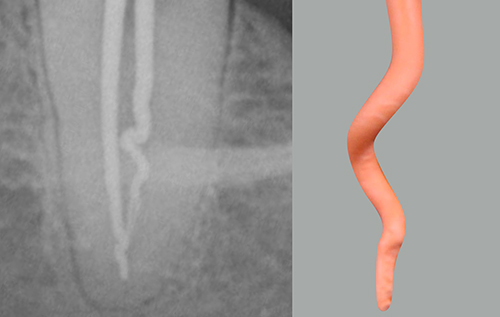

La prova del cono di guttaperca è uno dei passaggi fondamentali per ottenere una buona otturazione tridimensionale dello spazio endodontico e, allo stesso tempo, è uno step che permette di verificare la correttezza dei precedenti.

Un buon adattamento del cono permette di procedere immediatamente con l'otturazione del canale. Al contrario, se non è possibile reperire un cono che si adatti alla preparazione effettuata, è bene considerare la possibilità che la sagomatura non abbia un'adeguata tronco conicità e che sia necessario migliorarla prima di eseguire l'otturazione canalare [1,2].